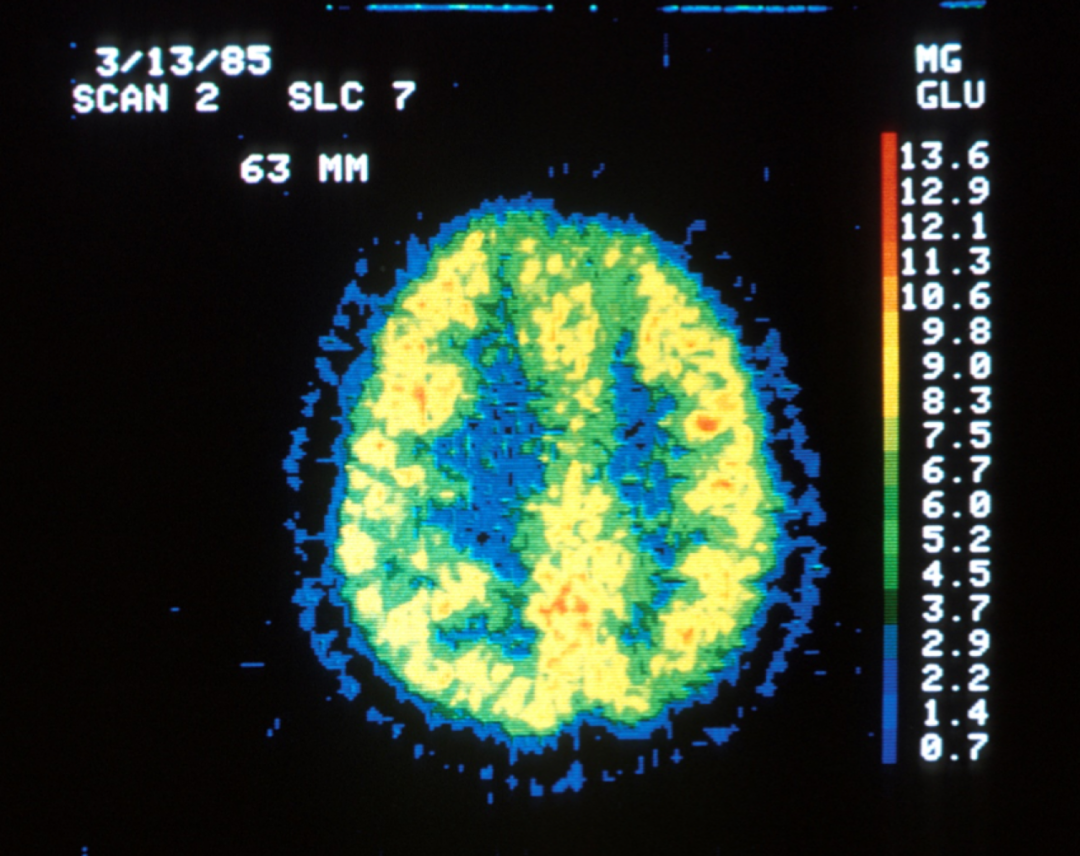

然而真实的PET扫描如下:

图片

从中,我们能看到,不管在做什么,大脑的神经元是不会有任何闲置的部分。各个部分都在承担它们应承担的功能,大脑全天候在线。